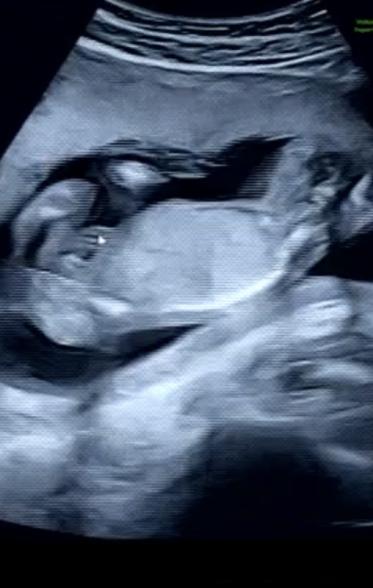

17w5d、性別は?

13wに胎児ドックを行った時には男の子かもと言われていましたが

17wでの検診の時には女の子だと言われました!

次の検診まで確定ではないとは言われていますが、、

赤ちゃんの性別についてですね。

拝見していて、はっきりと男の子のシンボルはわからず、女の子のサインとされるお股のあたりに見られるようになる葉っぱのマーク、サインが、添付をしてくださったものからは分かりませんでした。